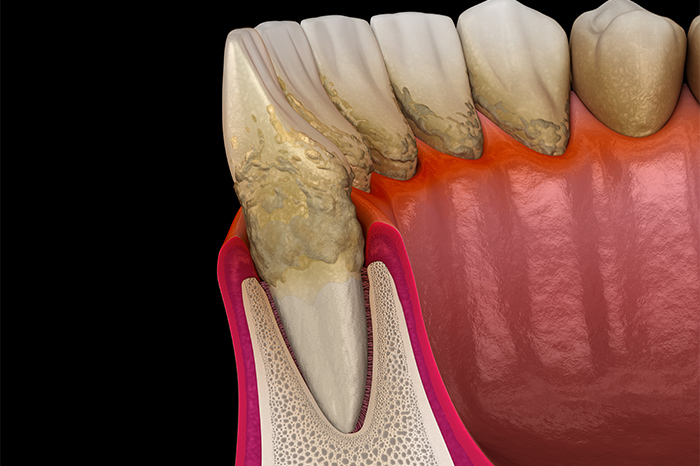

歯を失ってしまう要因の上位には、歯周病が該当します。初期段階では痛みや違和感などの自覚症状がほぼなく、いつの間にか進行してしまう厄介な疾患と言えます。歯周病の予防、および進行を食い止めるためには、日々の適切なブラッシングなどが大切ですので、ご自身でのケアをしっかりと行うように心がけましょう。

歯周病検査

歯周ポケット検査

歯と歯ぐきの隙間の深さを測定し、歯周病の進行度を確認します。炎症の有無や出血の状態を把握して、健康維持に必要なケア方法を明確にします。

SRP

Scaling and Root Planingの略であり、基本的な歯周病治療の方法です。スケーリングで歯の表面に付着した歯石を取り除き、ルートプレーニングで歯周ポケットの深い部分にある歯石も除去します。歯面を滑らかにして、歯石の再付着も防ぎます。

歯周外科処置

歯周病治療では、歯ぐきを切開して歯根を出して、歯石や細菌感染部分を除去する外科処置が行われることもあります。スケーリングなど基本的な治療では改善が難しい症例が対象となり、歯周組織の状態によっては再生療法も用いられます。